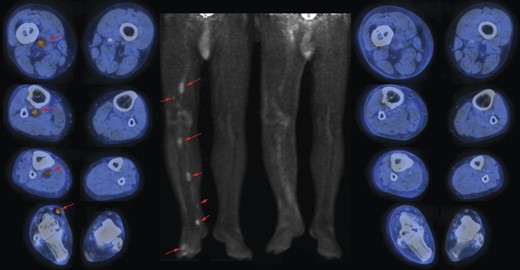

A 61-year-old male patient with no particular previous illnesses was diagnosed with a well-differentiated STMM of the plantar surface of the second toe of the right foot, with infiltrated margins after excisional biopsy. Microscopically, myoepithelioma consists of nests and cords of epithelioid, plasmacytoid or spindle cells, with inconspicuous nucleoli, mainly eosinophilic cytoplasm and, in some cases, clear cells. The cells are embedded in a chondromyxoid, collagenous or hyalinized stroma; no significant nuclear pleomorphism is usually observed and mitoses are scarce. The malignant variant is exclusively recognized by its histological features, showing a marked cytologic atypia, prominent nucleoli, necrosis and a high mitotic index (>7/10 HPF) [2, 5]. The patient underwent computerized tomography (CT) of the chest and abdomen for staging; the results were normal. Considering the residual disease in the previous excision of the nodule, the patient underwent a radical disarticulation of the toe 20 days after excisional biopsy. Three months later, the patient presented a lump on the plantar surface of the third toe of his right foot, a subcutaneous nodule on the right ankle and another nodule on the back of the foot; excisional biopsy of the latter showed de-differentiated STMM. Because of these findings, a positron emission tomography-CT (PET-CT) [7] was performed, which showed the presence of in-transit metastases in the right lower limb, extending to the middle third of the thigh. Ultrasound-guided fine needle aspiration cytology (FNAC) was performed at the level of the most accessible of these lesions, which confirmed secondary STMM (Fig. 1). The patient was then treated with hyperthermic isolated limb perfusion (HILP) using human recombinant tumor necrosis factor 1 mg and melphalan 90 mg. During the subsequent follow-up, a complete response was documented (Figs. 2 and 3).

On the left side: images (transaxials fused and maximum intensity projection) of pre-HILP 18F-fluorodeoxyglucose (18F-FDG) PET/CT showing areas (red arrows) of increased uptake representing in-transit metastases in the right lower limb, extending to the thigh; on the right side: images (transaxials fused images and maximum intensity projection) of post-HILP showing clear reduction of pathological uptake of 18F-FDG.